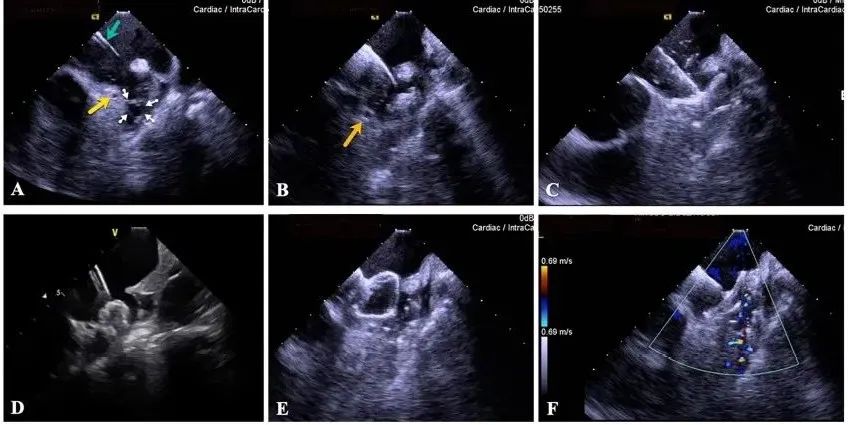

一種與心導(dǎo)管檢查相結(jié)合的超聲心動圖診斷新興技術(shù),通過將超聲探頭置于心腔內(nèi)部,發(fā)射并接收超聲信號,來精確獲取心臟解剖結(jié)構(gòu)、心臟血流動力學(xué)等信息的實時成像。與其他影像技術(shù)相比,ICE技術(shù)具有操作簡單、無輻射、安全性高、手術(shù)效率高、實用等優(yōu)勢,ICE在很大程度上有望取代經(jīng)食道超聲心動圖(TEE),成為電生理和結(jié)構(gòu)性心臟病領(lǐng)域的理想成像方式。

目前ICE技術(shù)已被應(yīng)用于左心耳封堵、房顫射頻消融、二尖瓣成形、房間隔缺損封堵等多種心臟介入手術(shù),應(yīng)用場景主要圍繞心臟電生理、結(jié)構(gòu)性心臟病等領(lǐng)域,目前以電生理應(yīng)用為主。數(shù)據(jù)顯示,我國結(jié)構(gòu)性心臟病介入器械市場規(guī)模已從2017年的4億元增長至2021年的20億元,年復(fù)合增長率達48.3%;預(yù)計到2025年,該市場規(guī)模將達到104億元,可以預(yù)見ICE市場規(guī)模也將同步高速增長,未來市場發(fā)展空間廣闊。

心腔內(nèi)超聲(ICE)技術(shù)壁壘極高,國內(nèi)主要廠商核心部件仍舊為進口,集成了超聲和圖像處理最前端技術(shù),包括超聲探頭、線纜、軟件成像算法等,是當(dāng)前內(nèi)窺超聲方向最具挑戰(zhàn)的領(lǐng)域。ICE的應(yīng)用經(jīng)歷了2D平面成像、3D三維立體成像、以及4D的實時三維立體成像階段。